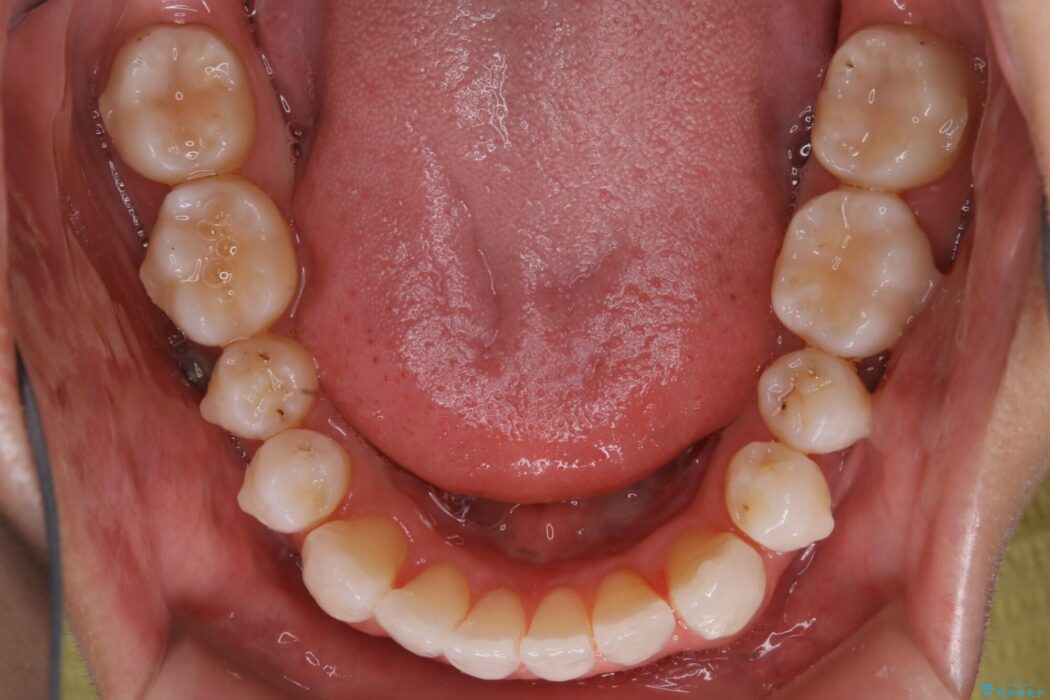

【20代男性】上顎のガタガタな歯列をインビザラインで矯正治療

上顎歯列弓のガタガタを治療したいとのことで来院されました。

前に出ていた前歯や目立つ八重歯(3番目の歯)もきれいに並び、奥歯の虫歯治療も並行して行ったため、機能面でも見た目的にも良くなり満足していただきました。